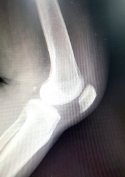

연골은 뼈와 뼈 사이에 있는 부드러운 조직으로, 뼈를 흡수하고 충격을 완화하는 역할을 합니다. 연골은 피부와 마찬가지로 세포가 없으며, 물질교환이 제한적인데, 이는 신체적인 외부 자극이 없기 때문입니다. 따라서 연골 손상은 자연치유가 어렵고 회복 속도가 느리며, 연골이 파괴된 경우에는 재생이 불가능할 수 있습니다. 연골 손상의 주요 원인으로는 부상, 나이, 비만, 축적된 스트레스 등이 있습니다. 연골을 보호하려면 규칙적인 운동과 올바른 자세, 영양소가 풍부한 식습관, 스트레스 관리, 적절한 수면 등이 중요합니다.

연골연화증은 연골 조직의 감소와 변성을 특징으로 하는 질환입니다. 연골은 우리 몸에서 충격 흡수 및 부드러운 움직임을 가능하게 해주는 뼈와 뼈 사이의 부드러운 조직입니다. 연골연화증은 연골 조직의 얇아지고 부족해지는 것으로 시작하여, 마지막에는 뼈 간 마찰이 발생할 수 있습니다.

연골연화증은 일반적으로 관절염, 골관절염, 노화, 부상 등과 같은 원인으로 발생합니다. 비만, 고혈압, 당뇨병과 같은 대사성 질환, 그리고 유전적인 요인도 연골연화증 발생에 영향을 줄 수 있습니다. 연골연화증의 증상은 관절 통증, 감각 이상, 운동 장애, 관절 변형 등이 있으며, 특히 무릎, 엉덩이, 손목 등의 관절에서 발생하기도 합니다.